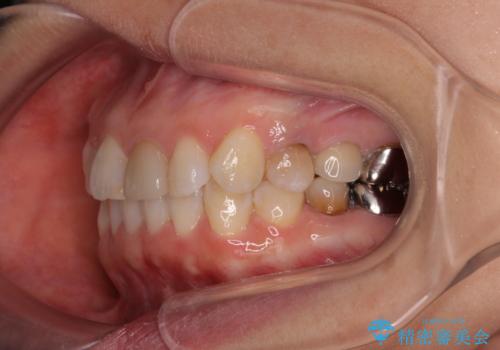

- 上下前歯のデコボコを気にして来院された患者様です。

カウンセリングにて詳しく話を聞いたところ、一番気になっているのは下顎前歯の叢生であり、上顎犬歯はあまり気になっていないとのことでした。

矯正治療は、歯の後戻りを抑制するために、治療終了後も保定装置をしっかりと使用していただくことが必須であるため、気になっている下顎だけを整えることで、その負担を半減できると考え、下顎のみの部分矯正として治療を行うこととしました。

装置としては、叢生の程度が強くなかったため、インビザラインの廉価版であるモデレート・パッケージを使用することとしました。